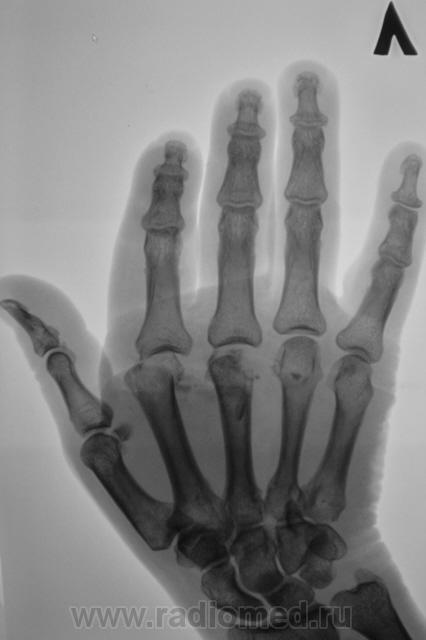

перелом 2,3,4 пястных костей.

Истины не знаю, но утверждает, что падал на кулак.

Пациент довольно пожилой. Общаться времени нет, синхронно идет три потока на трех аппаратах, да иногда еще и на "дентальный" дернут...